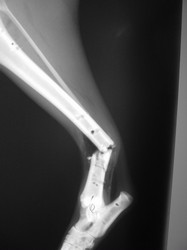

Fijación Externa

PRÁCTICAS CURSO DE FIJACIÓN EXTERNA PERFECCIONAMIENTO.

Híbrido.